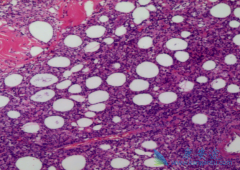

非霍奇金淋巴瘤 诊断必须依靠病理确诊。同时根据组织细胞形态特点,结合免疫表型和细胞遗传学特征可以明确病理类型,对指导个体化治疗用药和判断预后有益。发病率高并有代表性的非霍奇金淋巴瘤:1.B细胞类型。弥漫大B细胞淋巴瘤、滤泡淋巴瘤、套细胞淋 ...